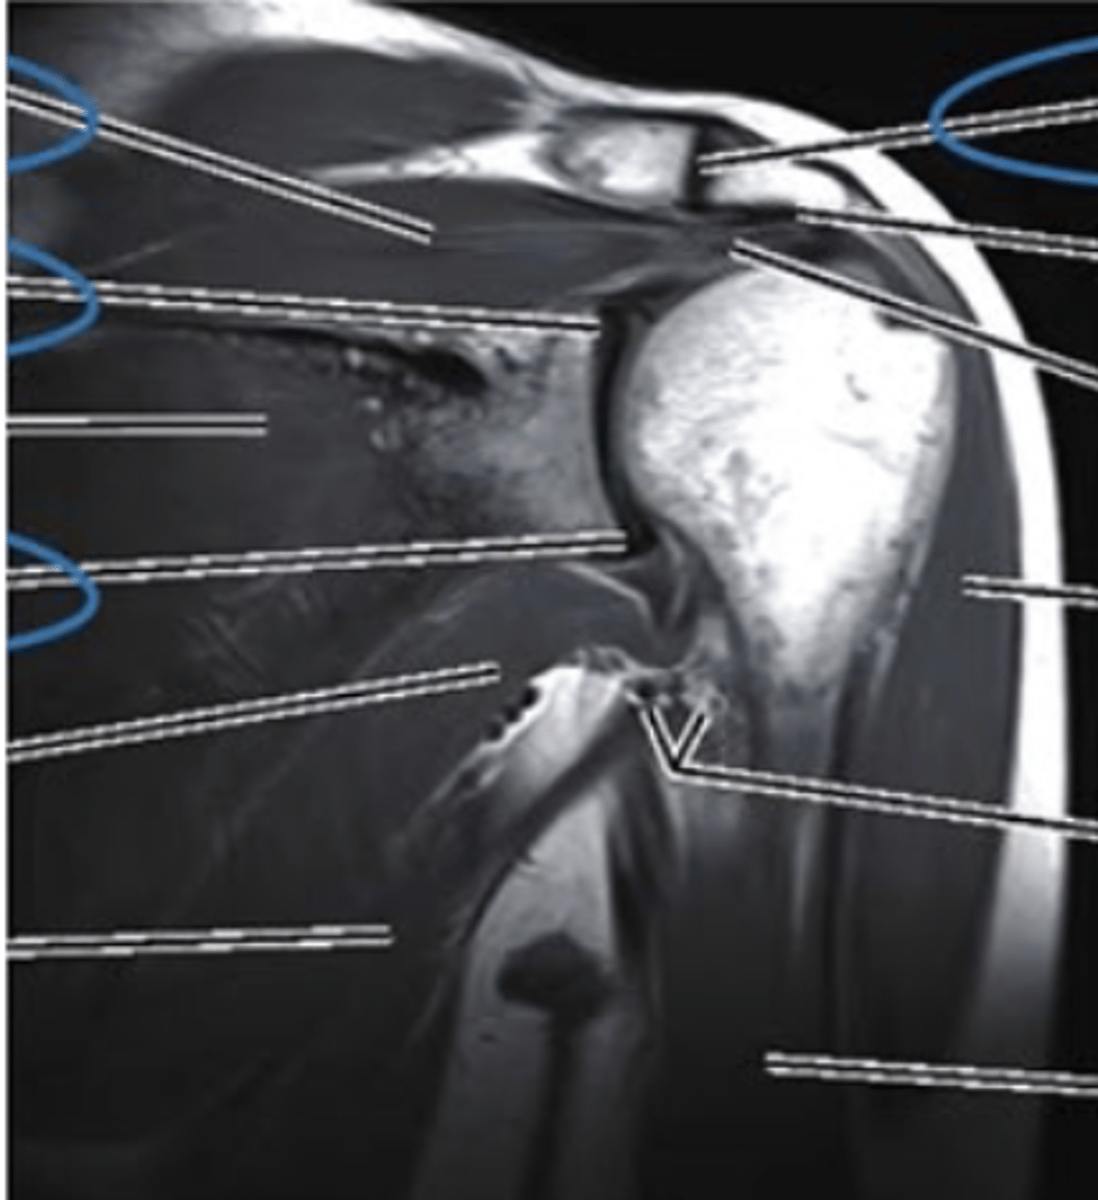

Coronal MRI

what imaging type and view is this?

AC joint

what does the pink line point to?

supraspinatus muscle

superior labrum

inferior labrum